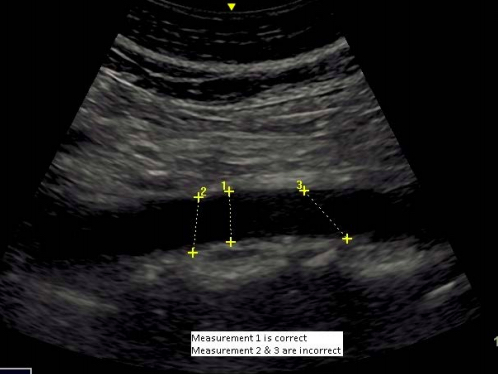

- Maximum anteroposterior diameter (inner to inner diameter) of the aorta perpendicular to the aortic wall should be measured at the lumbar level in both the transverse and longitudinal positions (see figure below for example of correct measurement in longitudinal position).

Image obtained from https://www.gov.uk/government/uploads/system/uploads/attachment_data/file/552720/NAAASP_scope_of_practice_document_V2.0_130916.pdf